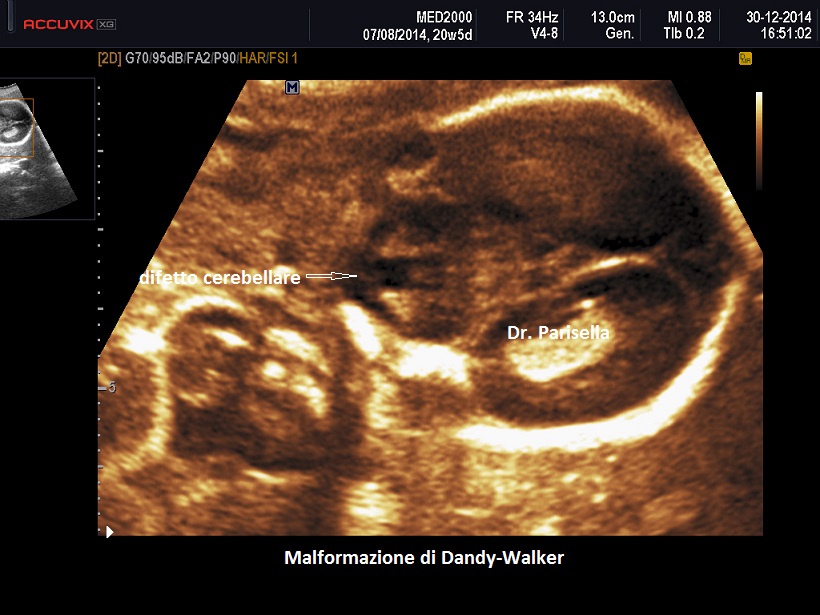

La diagnosi differenziale deve essere posta principalmente con la sindrome di Dandy-Walker: in tal caso è dirimente la presenza nella sindrome di Joubert del "segno del molare" e la familiarità.